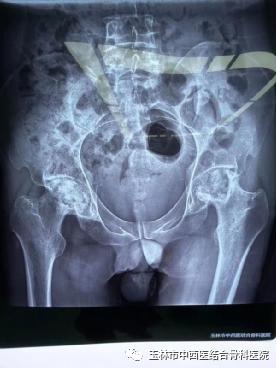

图一为患者术前DR结果

图二为患者髋关节置换术后DR结果

手术当日,髋关节一科黎观保主任带领团队在麻醉科、手术室的配合下为卢先生进行了直接前路(DAA)微创人工右髋关节置换手术。由于手术创伤小,术中几乎没有出血,对肌肉组织损伤也非常轻微,麻醉苏醒后的卢先生便可立即自主活动髋关节,能够轻松抬腿了,而且自觉没有明显疼痛感。

术后第一天就可在病房内不扶拐行走,没有明显跛行步态以及任何姿势的限制,还能完成深蹲、盘腿等动作,连病房里的病友都感叹手术的成功。其实,这一切主要归功于DAA。